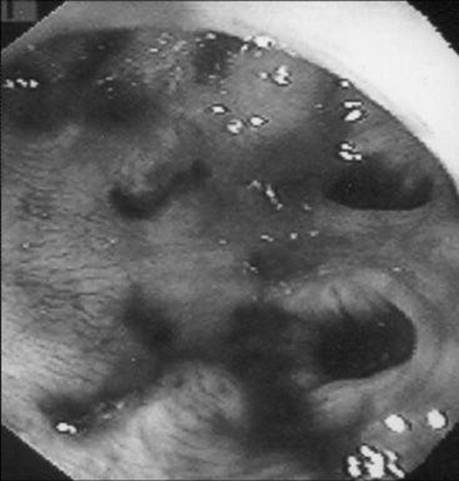

A 37-year-old man with a history of alcohol abuse is transferred to your hospital with a history of hematemesis and melena the day before. He has numerous spider telangiectasias on his upper body and mild asterixis. What lesion is being demonstrated on upper endoscopy?

Figure 1-1

Esophageal varices in the distal esophagus that have undergone band ligation.